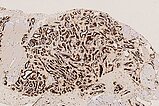

In der 130-fachen Vergrößerung (immunhistochemische CD31-Färbung zur Darstellung von Gefäßendothelien) zeigt sich eine intensive braune Anfärbung der endothelialen Strukturen. Dies beweist den Gefäßcharakter der Läsion. Die Gefäße sind beim infantilen Hämangiom als vaskulärer Tumor typisch lobuliert angeordnet.

In der 100-fachen Vergrößerung (SMA „smooth muscle actin“ zur Darstellung der glattmuskulären Perimyozytenschicht) wird die erhaltene, symmetrische Perimyozytenlage um jede dargestellte Kapillare verdeutlicht. Dies ist ein Kriterium für einen benignen vaskulären Prozess.

In der 130-fachen Vergrößerung (WT1-Färbung) spricht auch die zytoplasmatische Positivität (braune Anfärbung im Bereich der Endothelzellschicht) gegen eine vaskuläre Malformation und für einen vaskulären Tumor, also hier passend zu einem infantilen Hämangiom.

In der 250-fachen Ausschnittsvergrößerung der GLUT1-Färbung zeigen die Kapillaren des infantilen Hämangioms eine charakteristische immunhistochemische GLUT1-Expression (braune Färbung der Endothelzellschicht), die normalerweise lediglich in plazentaren Kapillaren und von diesen abgeleiteten vaskulären Tumoren eine Positivität zeigt. Daher auch die Annahme, dass sich infantile Hämangiome aus vaskulären Präkursorzellen der Plazenta ableiten. In anderen Hämangiomen (z. B. angeborenen Hämangiomen wie NICH oder RICH) ist GLUT1-negativ. Dies stellt das wichtigste differentialdiagnostische histologische Kriterium zum infantilen Hämangiom dar. Die in den Lumina enthaltenen Erythrozyten zeigen ebenfalls eine GLUT1-Positivität und dienen damit als positive interne Kontrolle, dass die Färbung technisch gut funktioniert hat.